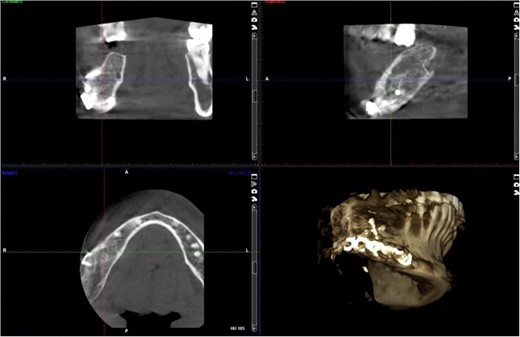

A 40-year-old woman presented with swelling on the right side of her mandible. She had completed orthodontic treatment 2 years earlier. A panoramic radiograph showed a unilocular radiolucency extending from the mandibular angle to the right first molar region (Figs 1–3).

The excised specimen’s histopathology confirmed its benign nature. One year postoperatively, the patient showed no infection or inflammation, with optimal mouth opening and mandibular movement. The reconstruction plate remained stable and intact (Figs 6 and 7).